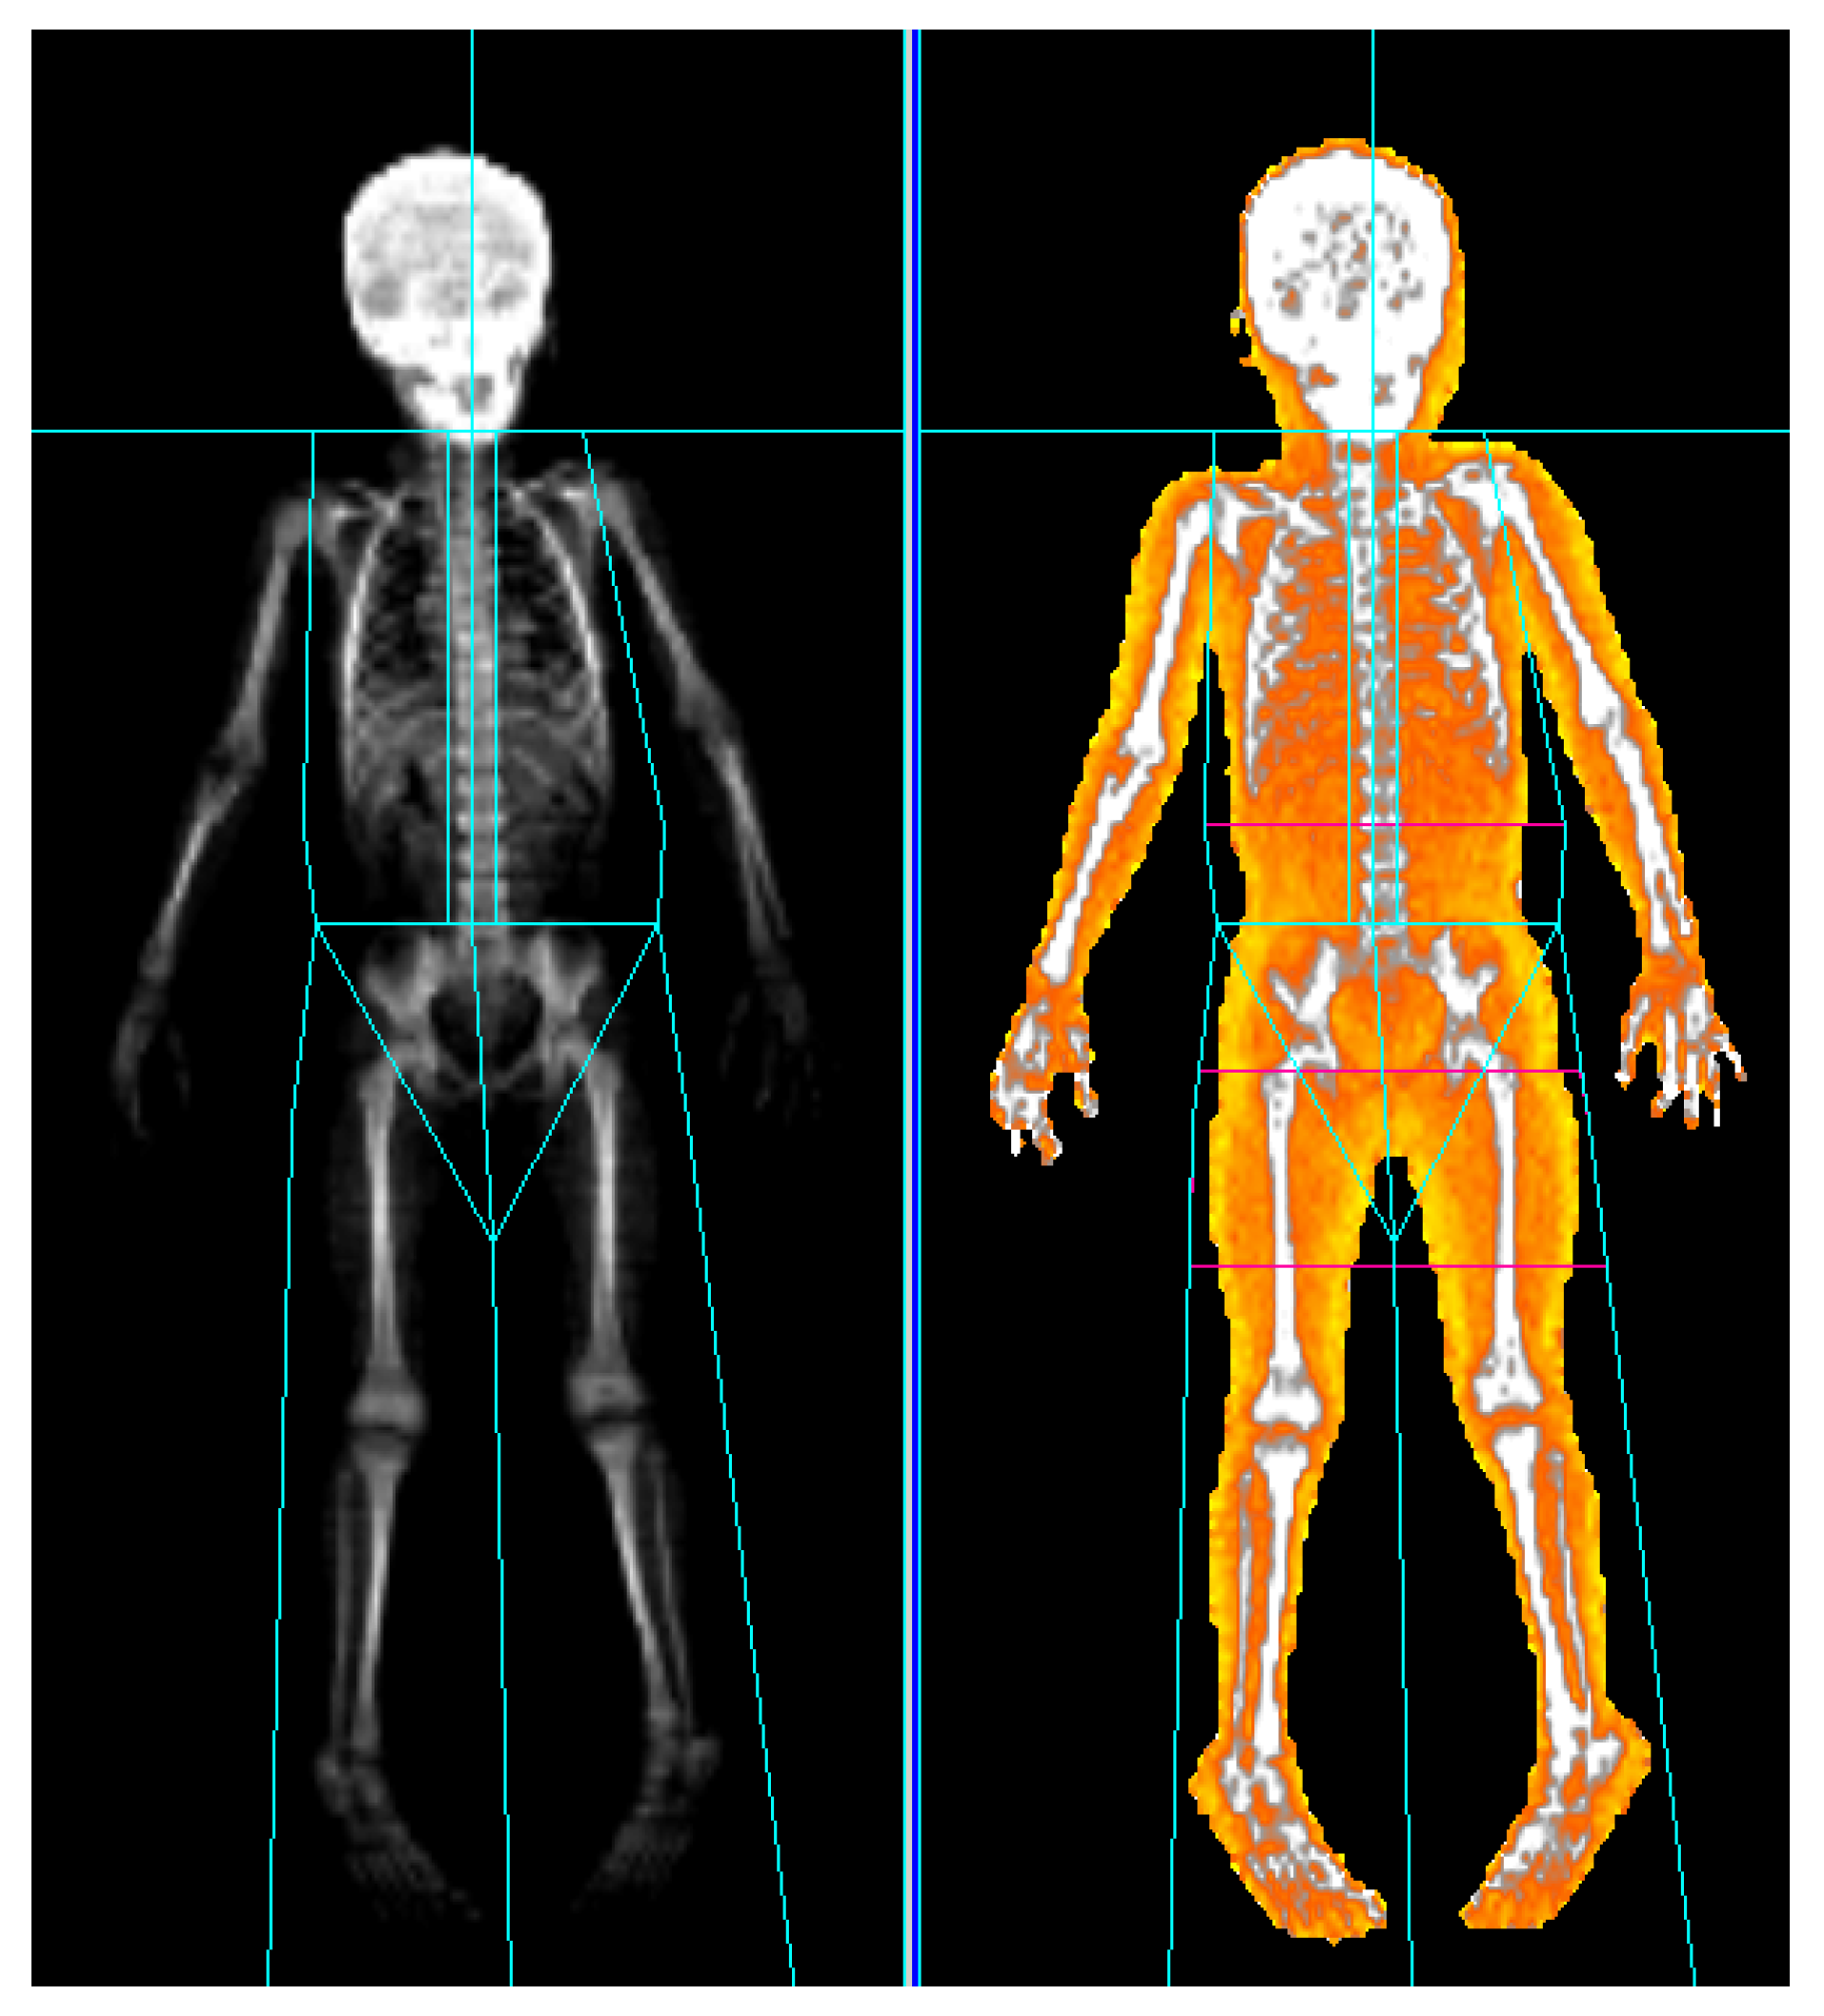

2.3. DXA Measurement